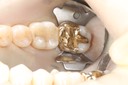

Kyle Chock #2 caries removal

Kyle Chock #2 prep